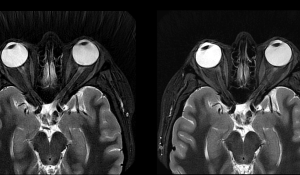

Moving beyond 2D, the AIR Recon DL platform’s 3D capabilities give physicians extra help in leveraging signal-to-noise (SNR) ratio and sharpness for more accurate and streamlined diagnostic processes. “By expanding AIR Recon DL to 3D and Propeller, GE Healthcare has closed the gaps in our ability to provide improved image quality and patient experience to all our patients across exam types, particularly for brain imaging, where we rely heavily on 3D sequences and musculoskeletal imaging, where Propeller is important for reducing image quality variability and eliminating repeat sequences due to motion,” said Dr. Tiron Pechet, a Shields Health Care Group radiologist and assistant medical director.

A recent study from GE Healthcare saw the entirety of its participants note improved SNR ratio and image sharpness. Though falling short of that impressive 100% figure, 99% of the study group also expressed that AIR Recon DL brings better or at least equivalent lesion conspicuity. The same report concluded that the solution can result in a 50% reduction in exam times. Its compatibility with Propeller motion-insensitive imaging sequencing make it a crucial add-on for physicians diagnosing and treating pediatric, neurodegenerative, geriatric, and claustrophobic patients.